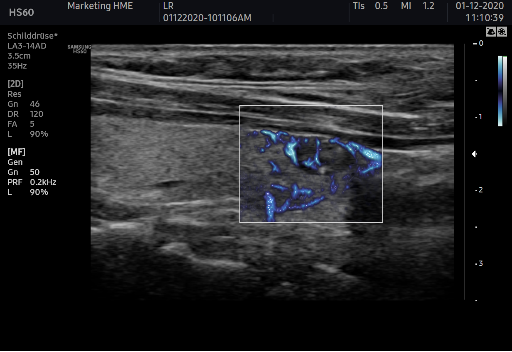

MV-Float  锐微成像

利用空间时间相干信息,提取低速血流,通过壁滤波器将组织运动带来的伪像滤去,用于观察微血管结构的血流动力学及血流灌注情况。拥有极高的时间分辨率及空间分辨率。在扫查甲状腺、乳腺等组织的低速血流时,优势明显。